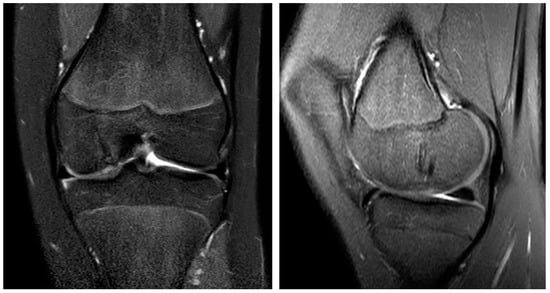

2. Case Report